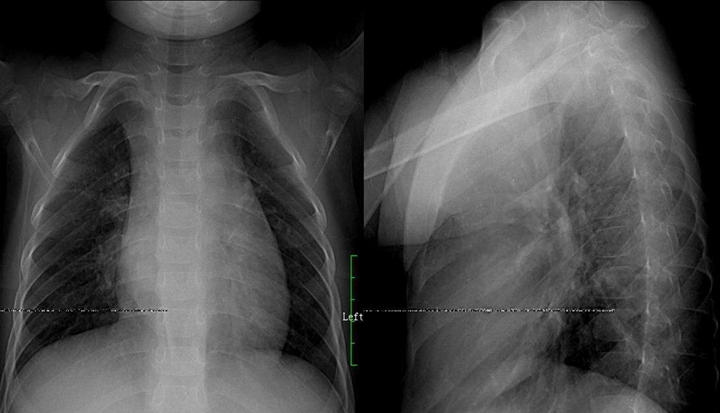

原发支气管肺癌:肺癌起源支上皮,组织大体类型别,中央肺癌四征像,不张气肿肿块肺炎,周围小癌边模糊,增大浓密边清楚,癌肿坏死空洞偏,脐凹兔耳癌索现,弥漫肺癌肺泡间,粟粒结节重叠囊。